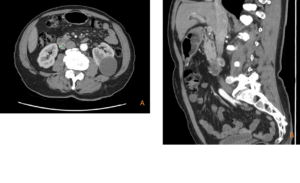

A 66-year-old male with a history of dyslipidemia, hypertension, and obstructive sleep apnea was referred for surgical evaluation after an incidental finding on abdominal computed tomography (CT). The contrast-enhanced CT revealed a 19 mm hypervascular, exophytic lesion in the second portion of the duodenum (D2). The patient was asymptomatic, denying abdominal pain, weight loss, gastrointestinal bleeding, or jaundice. Physical examination and laboratory workup (complete blood count, liver enzymes, bilirubin and tumor markers) were unremarkable.

Figure 1: Transverse (A) and sagittal (B) CT images showing a 19 mm hypervascular lesion in the D2